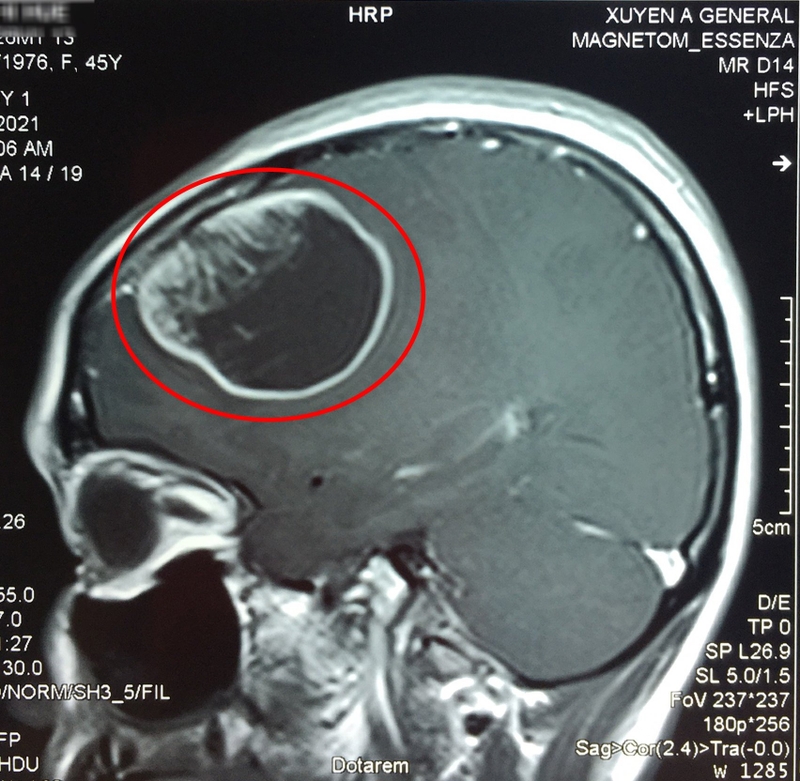

Kết quả của xét nghiệm sẽ quyết định phần lớn phương thức điều trị cho trẻ, giúp định vị trước mổ, đánh giá kết quả sau mổ và theo dõi điều trị. Các xét nghiệm thường được đề nghị là: